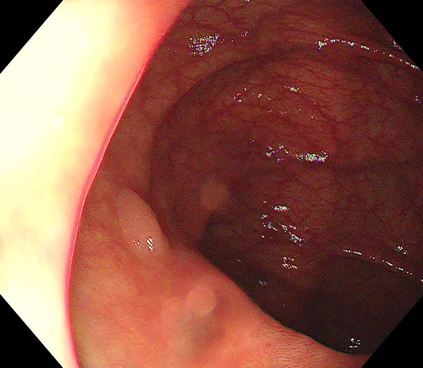

Polyps are early cancer indicators, so assessing occurrences of polyps and their removal is critical. They are observed through a colonoscopy screening procedure that generates a stream of video frames. Segmenting polyps in their natural video screening procedure has several challenges, such as the co-existence of imaging artefacts, motion blur, and floating debris. Most existing polyp segmentation algorithms are developed on curated still image datasets that do not represent real-world colonoscopy. Their performance often degrades on video data. We propose a video polyp segmentation method that performs self-supervised learning as an auxiliary task and a spatial-temporal self-attention mechanism for improved representation learning. Our end-to-end configuration and joint optimisation of losses enable the network to learn more discriminative contextual features in videos. Our experimental results demonstrate an improvement with respect to several state-of-the-art (SOTA) methods. Our ablation study also confirms that the choice of the proposed joint end-to-end training improves network accuracy by over 3% and nearly 10% on both the Dice similarity coefficient and intersection-over-union compared to the recently proposed method PNS+ and Polyp-PVT, respectively. Results on previously unseen video data indicate that the proposed method generalises.